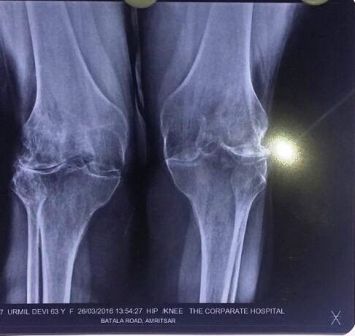

Patient : Mrs. Urmil Devi

Age / Sex : 63 yrs Female

• A case of Rheumatoid Arthritis from last 20 years.

• Fixed Flexion Deformity both knee joints 90 degrees.

• Wasting of Quadriceps and Hamstring Muscle rejected from many surgeons.